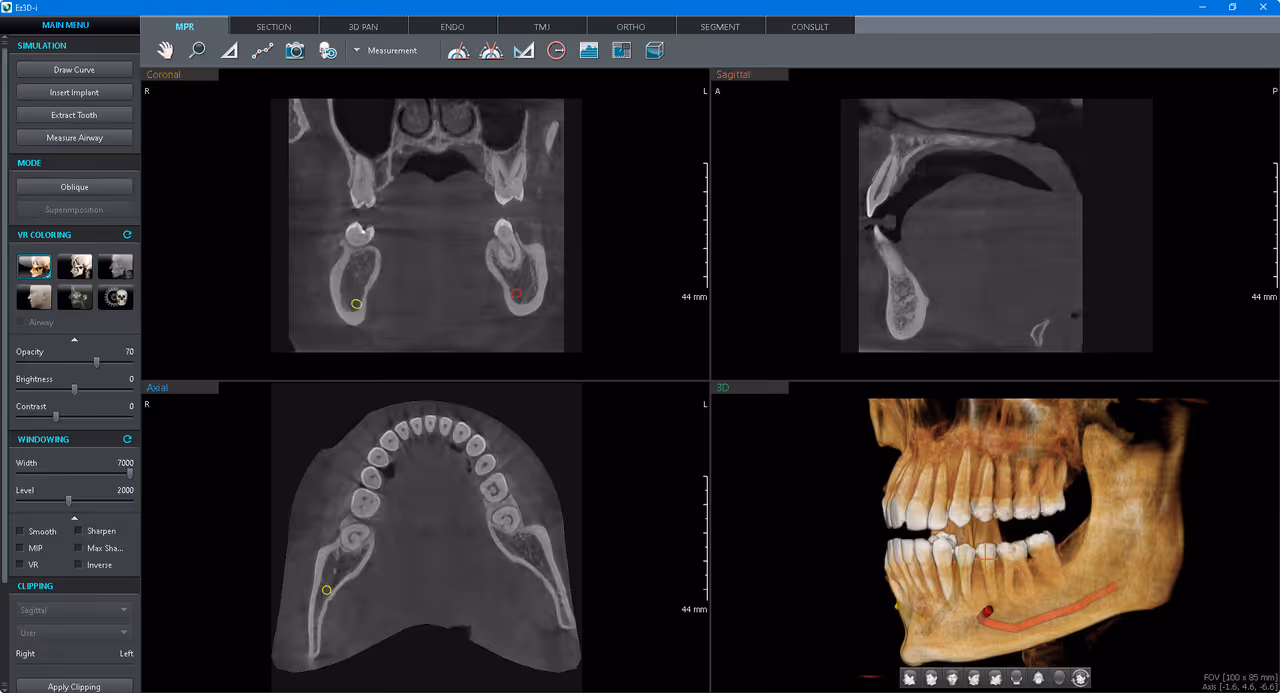

Our office utilizes the latest technology and equipment to provide better, more precise care. CBCT or 3D CT dental scans are now the standard of care for dental implant planning and surgery, wisdom teeth extractions, and root canal therapy.

A 3D CT dental scan, also known as Cone Beam Computed Tomography (CBCT), is an advanced, low-radiation imaging technology that creates detailed, 3D digital models of teeth, jawbones, nerve pathways, and soft tissues in seconds. It provides superior accuracy over traditional 2D X-rays for planning implants, oral surgery, and diagnosing complex dental issues.

- Dental Implant Planning: It is considered the gold standard for measuring bone density and volume to ensure safe and accurate implant placement. Learn more about our approach to dental implants.